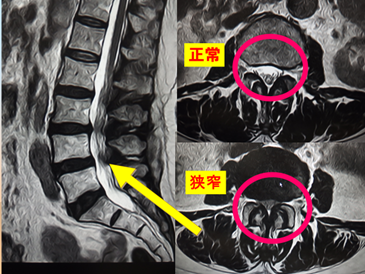

⑦右ひざの外側が痛くて、歩くと次第に痛みが強くなる

じつは…

腰部脊柱管狭窄症(ようぶせきちゅうかんきょうさくしょう) (腰の神経が狭い)

つまり、ひざばかりをみていても診断は出来ません。